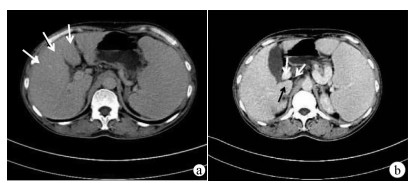

Clinical features of culture-negative liver abscess

Jianhong HAO, Na YAO, Minyuan BI, Gufen ZHANG, Linxu WANG, Jianqi LIAN, Chunfu WANG

2021, 37(1): 110-114. DOI: 10.3969/j.issn.1001-5256.2021.01.022

Abstract(1223) HTML (240) PDF (2057KB)(81)

Abstract:

Objective  To investigate the clinical features and prognosis of culture-negative liver abscess (CNLA) versus culture-positive liver abscess (CPLA), and to provide a reference for early diagnosis and effective treatment.  Methods  A retrospective analysis was performed for the clinical data of 371 patients with liver abscess who were admitted to The Second Affiliated Hospital of Air Force Medical University from 2005 to 2018, among whom 145 (39.1%) had positive results of pathogen test (CPLA group) and 226 (60.9%) had negative results (CNLA group). The two groups were compared in terms of clinical features, laboratory examination, imaging data, and prognosis. The t-test was used for comparison of normally distributed or approximately normally distributed continuous data between two groups, and the Mann-Whitney U test was used for comparison of non-normally distributed continuous data between two groups; the chi-square test or the Fisher's exact test was used for comparison of categorical data between two groups.  Results  Compared with the CNLA group, the CPLA group had a significantly older age (t=-3.464, P=0.001) and a significantly higher proportion of patients with diabetes (χ2=17.362, P < 0.001) or cardiovascular disease (χ2=10.827, P=0.001), and compared with the CPLA group, the CNLA group had a significantly higher proportion of patients with AIDS (χ2=4.354, P=0.037). Compared with the CNLA group, the CPLA group had significantly greater increases in leukocyte count, percentage of neutrophils, alkaline phosphatase, gamma-glutamyl transpeptidase, and total bilirubin (U=20393, 19711, 18586, 19349, and 18496, all P < 0.05), a significantly greater reduction in albumin (t=3.348, P=0.001), and a significantly higher proportion of patients with a baseline APACHE Ⅱ score of ≥16 (χ2=9.550, P=0.002). Compared with the CNLA group, the CPLA group had a significantly higher proportion of tumors with a diameter of > 5 cm (χ2=53.61, P < 0.001). In the CNLA group, 19.9% of the patients were treated with anti-infective therapy alone, while for both groups, anti-infective therapy combined with ultrasound- or CT-guided percutaneous drainage was the main treatment method. There were no significant differences in the length of hospital stay, recurrence rate, and mortality rate between the two groups (all P > 0.05).  Conclusion  Compared with CPLA patients, CNLA patients tend to have a younger age and are less likely to develop severe inflammatory response and liver insufficiency, with a smaller diameter of abscess which is less likely to be treated by percutaneous drainage, while there is no significant difference in prognosis between CPLA patients and CNLA patients.